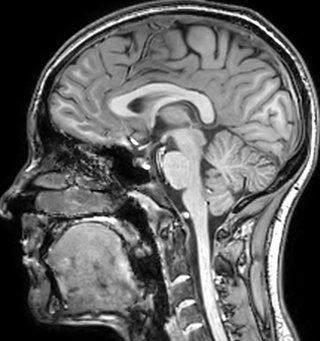

QSM elition Kames algorithm

QSM based on a Compressed SENSE multi-echo SWI.